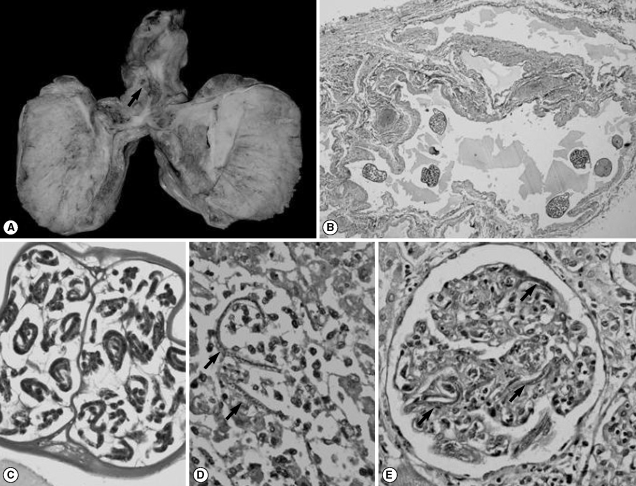

A 21-year-old male presented with progressive breathlessness for the past 2 months with pain in the right upper quadrant of the abdomen for 4 days duration. He also complained of cough with scanty expectoration and high grade fever of similar duration. There was no history of pedal edema, decreased urine output, abdominal distention, chest pain, or palpitation. On examination, he had tachycardia with raised blood pressure (160/90 mm of Hg), but the other vitals were stable. The jugular venous pressure (JVP) was normal. There was tenderness in the right upper quadrant with hepatomegaly. The spleen was not palpable and no ascitis was noted. Cardiovascular system examination revealed a loud S2 with a pansystolic murmur in the tricuspid area. Chest examination revealed bilateral crepitations. Investigations revealed leucocytosis (TLC-16,800) with mild eosinophilia (16%). Renal function tests were deranged with raised blood urea (75 mg/dl) and serum creatinine (1 mg/dl). Chest X-ray showed an opaque left hemithorax, and on ultrasonography a large, well defined, anechoic cystic lesion was seen occupying the entire left hemithorax with multiple septations (Fig. 1A), suggesting the possibility of a hydatid cyst. The liver span was 12 cm with normal echotexture. Microscopic examinations of the pleural fluid revealed 2,800 pus cells with 2 mg/dl sugar and 6 g/dl proteins. The patient was treated with injection of Lasix and antibiotics; however, his condition soon deteriorated and he succumbed to his illness with cardiorespiratory arrest.

A partial autopsy was performed following an informed consent. Mild bilateral scrotal sac enlargement was noted. There was bilateral pleural effusion with 1,500 ml of straw colored fluid and bilateral hydrocoele with 20 ml of fluid in the scrotal sac. Both lungs weighed 730 g, and there was marked pleuritis with fibrinous tags (left > right). A large multi-loculated pleural based cyst (10 × 8 × 3 cm) filled with thick greenish material was present on the left side (Fig. 1B). Multiple tiny nodular lesions (4-5 mm) were palpable in the rest of the lung parenchyma. Microscopically, the cyst was confirmed to be a loculated empyema with outer fibrous wall, scattered giant cells, and the lumen filled with fibrin-rich acute inflammatory exudate chiefly comprising of eosinophils (Fig. 1C). Also seen in the cavity wall were many sheathed microfilariae of Wuchereria bancrofti (with absence of characteristic fine nuclei in the tail) (Fig. 1D). Other areas revealed features of tropical pulmonary eosinophilia (TPE) with eosinophilic alveolitis and bronchitis (Fig. 1E). A large thrombus was noted in the main pulmonary artery with large areas of infarction, and adjacent areas showed presence of heart failure cells within the alveoli.